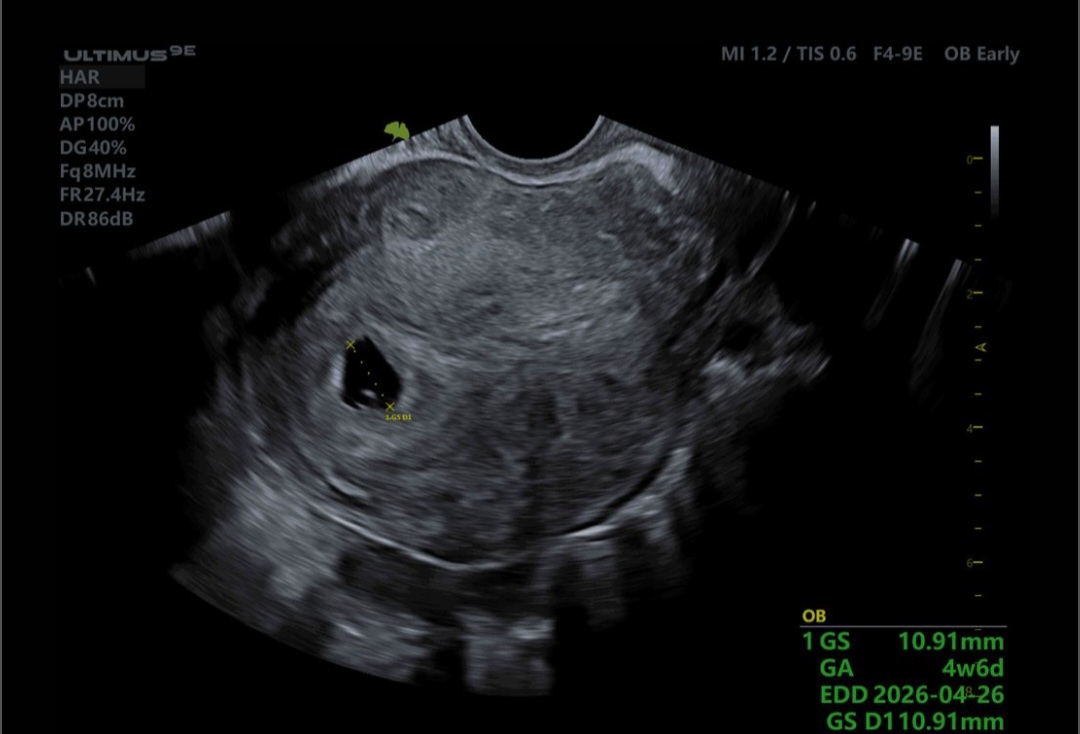

چشم من امشب ساعت ۶و نیم وقت سونو دارم نتیجه رو ارسال میکنم

پزشک اوما

چشم هاتون بی بلا جانم همینجا ارسال کنید تا ببینم

واااای خداروشکر خارج رحمی نیست

تازه 5 هفته ای

جان دلم خداروشکر خارج رحمی نیست بنظر من یکی دو روز به خودتان فرصت دهید با آرامش درمورد این مساله فکر کنید برای سقط عجله نکنید چون میتوان به بارداری امید داشت

طبق پریود ۶ هفته و ۴ روزم